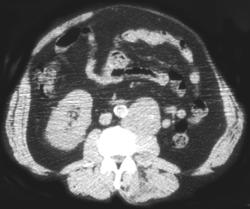

Post CT Angio Topograms for Calyceal Anatomy